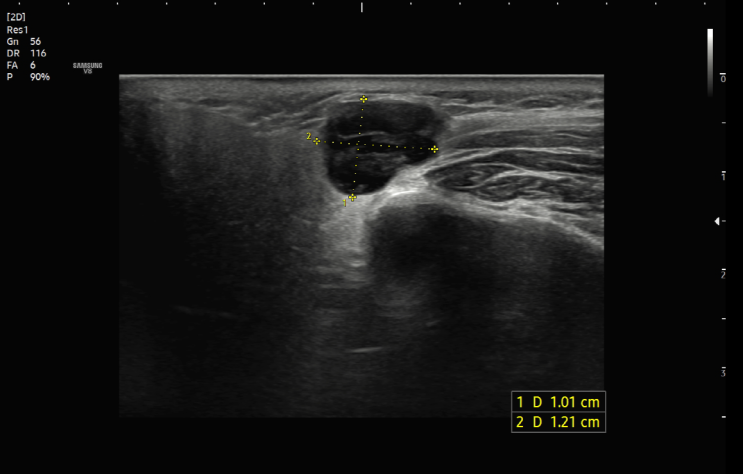

[왕십리 경부초음파] 서울으뜸내과, 목에 만져지는 멍울로 진단된 림프종

#서울으뜸내과 #목초음파 #경부초음파 #림프절비대 #림프종 #왕십리검진내과 #상왕십리검진내과 #행당동검...